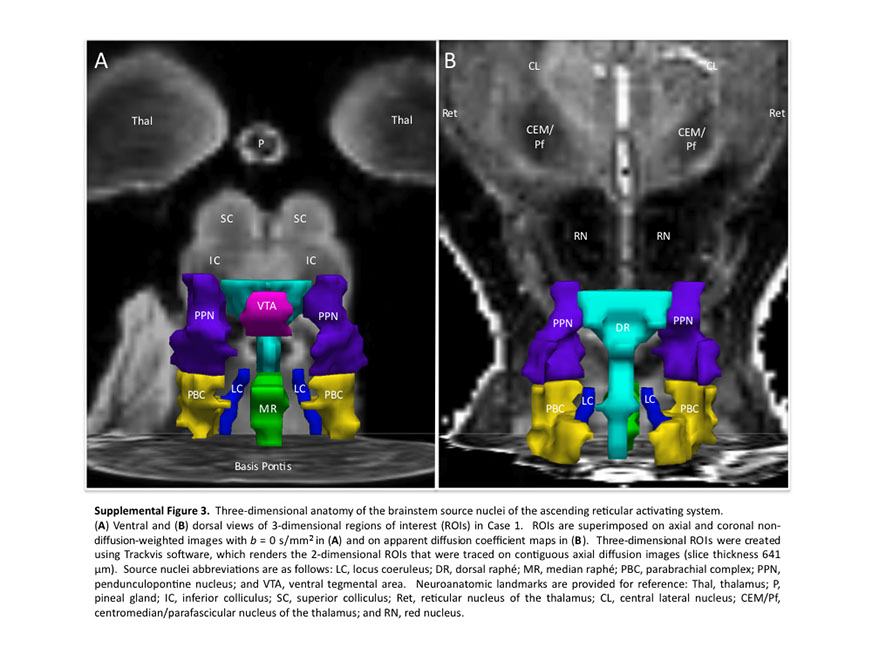

Many observations suggest that CFS could derive from residual damage to the reticular activating system (RAS) of the upper brain stem and/or to its cortical projections. It should be pointed out that although the larger right greater than left asymmetry in regional cerebral blood flow is found at the parietotempotal level in CFS patients as compared to healthy controls, no significant correlations are found between frontal tracer uptake and right-left parietotemporal asymmetry, on the one hand, and clinically relevant CFS dimensions on the other. Damage to the RAS could be produced by a previous viral infection, leaving functional defects unaccompanied by any gross histological changes.

In this respect, fluorine-deoxyglucose positron emission tomography showed specific metabolism abnormalities in CFS patients (hypometabolism in right mediofrontal cortex and brainstem) as compared with both healthy controls and depressed patients. The most relevant abnormality is brain stem hypometabolism, which has been also reported in single-photon emission computed tomography studies and seems to be a marker for the in vivo diagnosis of CFS